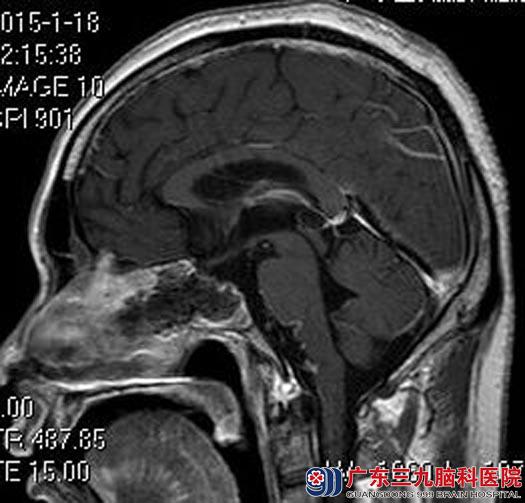

由鲁明主任主刀,急诊全麻下行经鼻蝶鞍区肿瘤切除术,术中显微镜下见肿瘤卒中,质地较韧,破入蝶窦,予肿瘤全切。术后汤先生视力基本正常,头痛明显好转,无脑脊液漏、尿崩等并发症。术后病理结果:垂体腺瘤并卒中。

手术后